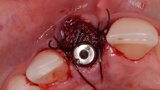

Figura 4. Exodoncia del diente.